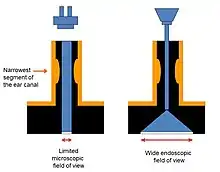

Traditionally, ear surgery has been performed using the surgical microscope. The direct line of view dictated by that approach necessitates using the mastoid as the access port to the middle ear. It has long been recognized that failure in cholesteatoma surgery occurs in some of the out of view spaces of the tympanic cavity like the sinus tympani and facial recess that are out of view using the traditional microscopic technique.[23] More recently, the endoscope has been increasingly utilized in the surgical management of cholesteatoma in one of two ways:

- The endoscope's wide angle of view and the ability to "see around the corner".[26]

- The endoscope allows minimally invasive access through the natural ear canal, rather than through the usual 5 cm incision behind the ear utilized in traditional microscopic surgery.[26]